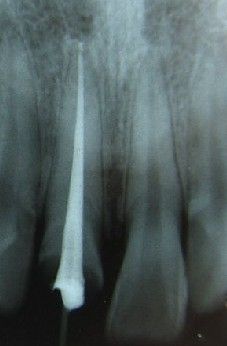

七、根管充填

封闭整个根管系统、堵塞主根管和侧副根管出口、防止微生物和液体的渗漏。无论是侧方加压法还是垂直加压法,应做到根管充填致密,根管充填后X线片上无根管腔隙,也不能超出根尖孔。立即咨询根管治疗价格<<